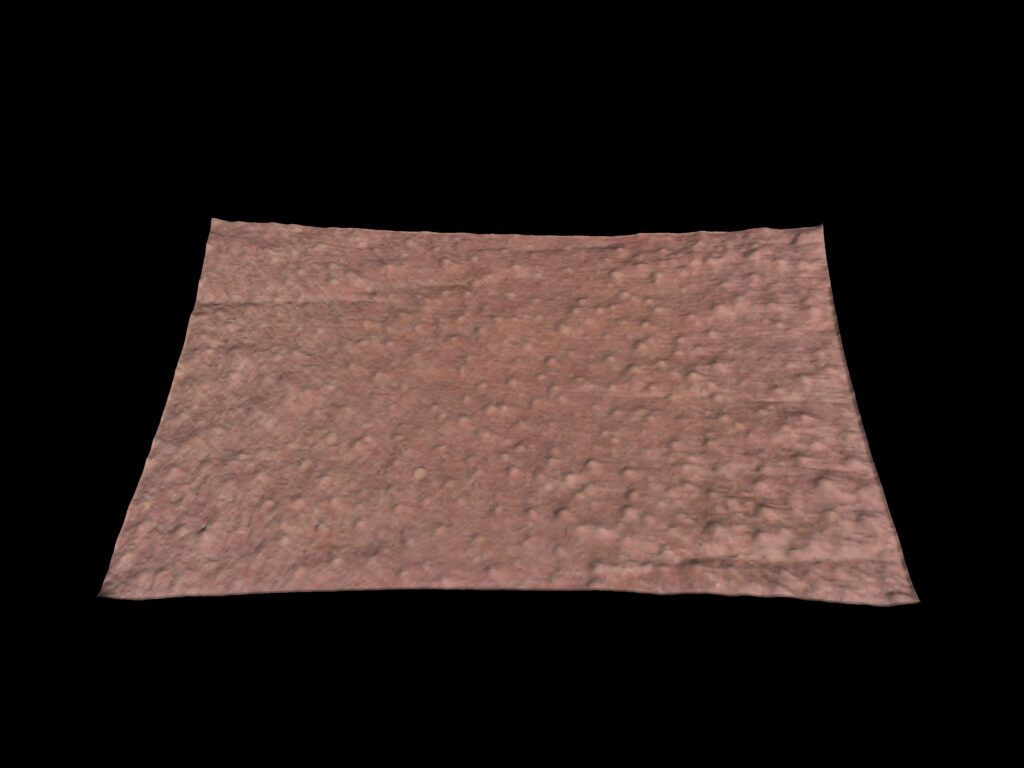

Roughness evaluation

The C-Cube is undeniably the best option for evaluating even the most subtle changes. Beyond measuring pimple elevation, it is able to observe very small signs of acne before they worsen with inflammation. This is equivalent to measuring the texture of the skin, invisible to the naked eye.

This can provide information about future cysts that may become inflamed in the following days.

3D analysis provides an additional dimension of pore depth. The 3D approach improves the sensitivity of pore detection. It can then be used to assess the depth of the pores and their possible filling.